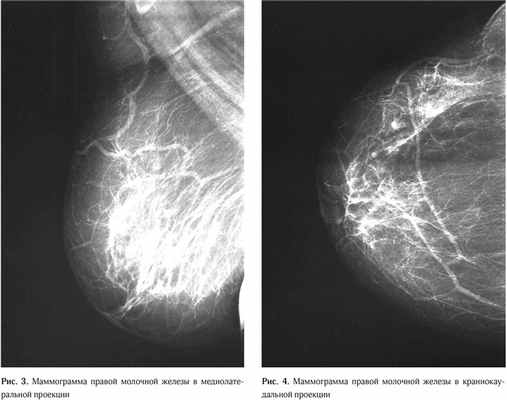

Результаты маммографии (03.04.2015 г.): молочные железы полусферической формы, симметричные. Контуры кожи и соски желез не изменены. Ретромаммарное пространство не затемнено. В обеих железах ткань представлена рассеянными фиброгландулярными уплотнениями. На границе латеральных квадрантов левой молочной железы обнаруживается асимметрия железистой ткани за счёт её увеличения. Заключение: диагностическая категория BI-RADS (Breast Imaging Reporting and Data System): справа – 2; слева – 3. Категория ACR (American College of Radiology): справа – 2; слева – 2 (Рис. 1–4).

В виду того, что данные маммографии в стандартных проекциях были малоинформативные, была выполнена прицельная маммограмма левой молочной железы с дозированной компрессией, что позволило более чет ко визуализировать участок нарушения архитектоники ткани, оценить его размеры и точную локализацию (Рис. 5).